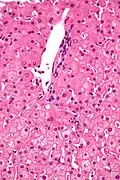

Micrograph showing ground glass hepatocytes. H&E stain. -

In liver pathology, a ground glass hepatocyte, abbreviated GGH, is a liver parenchymal cell with a flat hazy and uniformly dull appearing cytoplasm on light microscopy. The cytoplasm's granular homogeneous eosinophilic staining is caused by the presence of HBsAg.

The appearance is classically associated with abundant hepatitis B antigen in the endoplasmic reticulum, but may also be drug-induced.[1][2] In the context of hepatitis B, GGHs are only seen in chronic infections, i.e. they are not seen in acute hepatitis B.